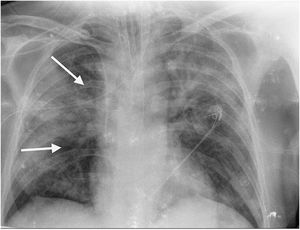

This is the case of a 64-year-old man with a past medical history of hypertension admitted to the ICU with a diagnosis of severe ARDS due to COVID-19-related bilateral pneumonia. The thoracic x-ray reveals a bilateral alveolar-interstitial pattern with damage to the right lung, especially the mid field (Fig. 1, pointer arrows). The blood test results show very high D-dimer levels (28970ng/mL) and due to suspected PTE, a thoracic echocardiography is performed that reveals the presence of RV pressure overload with positive McConnell sign. Following the echocardiographic findings, anticoagulant therapy with low-molecular weight heparin (enoxaparin 1mg/kg/every 12h) is initiated. A thoracic CCTA was performed for diagnostic confirmation purposes that revealed the presence of a repletion defect in the artery of the medial lobe lateral segment (arrows in Figs. 2 and 3) in the PTE setting. Also, the presence of diffuse bilateral damage and extensive areas of cobblestone pattern in a viral infectious process setting (Figs. 2 and 3). The patient remained on anticoagulant therapy until hospital discharge without any associated bleeding complications.